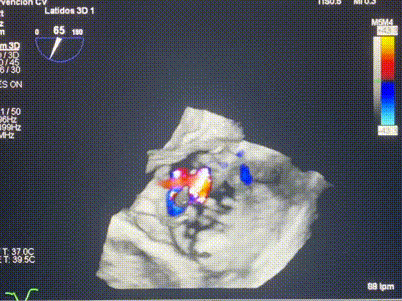

術中輸送器在超聲引導下調(diào)整位置

手術在全麻狀態(tài)下進行。術者采用經(jīng)右側頸靜脈入路的方式將輸送器送入患者心臟內(nèi),在TEE及DSA引導下調(diào)整輸送器頭端角度,使得輸送器與三尖瓣瓣環(huán)平面垂直。在輸送器進入右心室后釋放室間隔錨定裝置,而后釋放瓣葉夾持件(2個耳片結構)成垂直狀態(tài)。在TEE及DSA確定夾持件固定至三尖瓣葉根部且位于右室側后釋放人工瓣心房側盤片。隨后調(diào)整瓣膜同軸性以及室間隔錨定件位置(貼合室間隔),前推藏針管并固定,進而釋放室間隔錨定裝置,并再次確認瓣膜位置、穩(wěn)定性及同軸性,合攏輸送鞘后撤出輸送器,完成LuX-Valve Plus人工三尖瓣瓣膜的植入,僅殘余微量瓣周漏。且經(jīng)手術中心電生理團隊評估,病人的起搏器和ICD功能沒有受到影響。